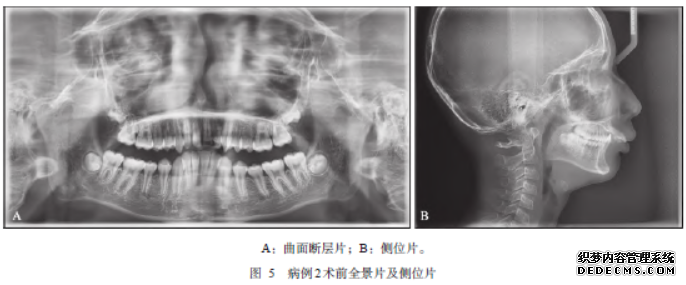

患者杨某,男,11岁。于2019年8月13日因“开口受限1+月”于四川大学华西口腔医院就诊。入院查体:颌面部基本对称,下颌后缩;最大自由开口度22mm;开口型无偏斜;触诊髁突滑动度下降,无弹响;双侧髁突无明显压痛及运动疼痛,咀嚼肌扪诊无压痛;恒牙列期(图5A),深覆盖正常覆牙合(图5B)。CBCT示:双侧冠突增长,高于髁突水平(图6A~D),髁突顶水平的轴位CT截面仍可见冠突影像(图7D),Dicom数据三维重建显示双侧冠突明显增生伸长,大张口时冠突与颧骨上颌骨交界处紧贴(图7A~C),双侧髁突未见明显异常。